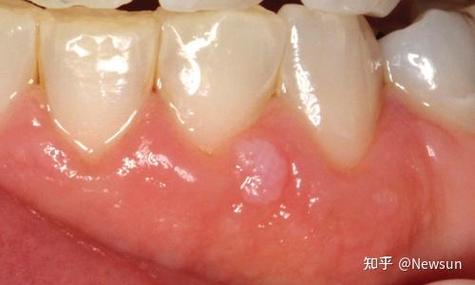

(图片来源网络,侵删)

- 位置:最常见于软腭、悬雍垂(小舌头)、舌下系带、牙龈、颊黏膜和嘴唇内侧,喉部(声带)也可能发生,但相对少见。

- 外观:

- 初期:可能表现为单个或多个微小的、淡红色或粉红色的丘疹,质地柔软,有时不易察觉。

- 典型形态:随着病情发展,会逐渐增大、增多,形成菜花状、乳头状或鸡冠状的赘生物。

- 颜色:颜色多为白色、粉红色或灰白色。

- 触感:通常无痛,但触摸时可能有颗粒感或粗糙感,如果继发感染,可能会出现疼痛、出血或异味。

- 大小:大小不一,从几毫米到几厘米都有可能。